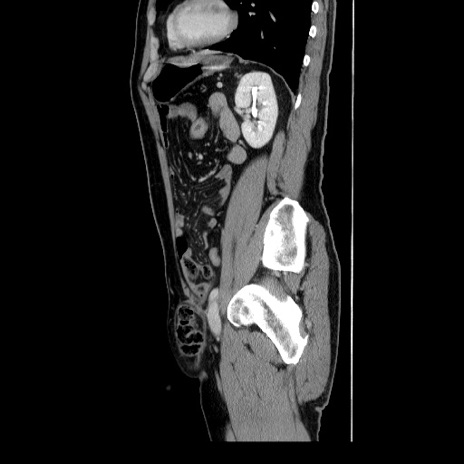

症例34(矢状断像)

【症例】60歳代 男性

【主訴】右鼠径部膨隆

【現病歴】1年程前より右鼠径部膨隆あり。自己にて還納可能だったため放置していた。3時間前より右鼠径部の脱出を認め、還納困難となり受診。

【身体所見】右鼠径部に小児頭大の膨隆あり。弾性硬であり、用手還納は困難。左鼠径部にも膨隆を認める。脱出はなし。